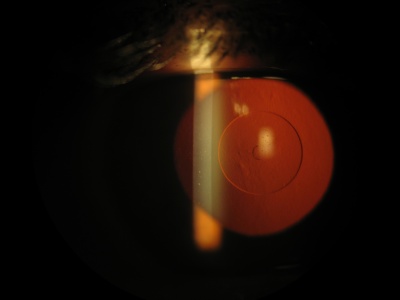

3. Small aperture inlays

These inlays are opaque, ring shaped with a central aperture. Based on the principle of pinhole optics, they improve near vision by increasing the depth of focus. The ring blocks the peripheral light rays and allows only the central rays to pass unhindered.

The Kamra Inlay (AcuFocus, Inc., Irvine, California, USA), previously known as ACI 7000, is an opaque ring shaped inlay made of polyvinylidene fluoride and carbon. It is 5 microns thick with an outer 3.8 mm diameter and a central 1.6 mm aperture. The ring has 8400 laser etched holes to facilitate diffusion of aqueous, oxygen and nutrients through the cornea. It is commercially available in the United States, Europe, Asia-Pacific, South America, and the Middle-East.